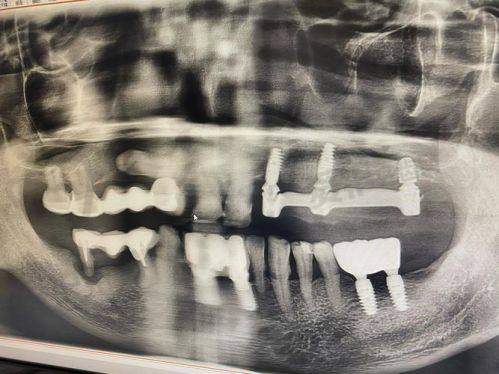

术前检查和评估:患者首先需要到医院进行全方面的口腔检查,包括口腔X光片、CT扫描等,了解口腔内部的情况,如牙槽骨的密度、高度、宽度等。医生会根据检查结果评估患者是否适合进行全口牙种植手术,并制定个性化的种植方案。

种植体植入手术:在局部麻醉下,医生会在患者的牙槽骨上制备种植窝,然后将种植体植入其中。手术过程中患者一般不会感到明显的疼痛,但术后可能会有轻微的肿胀和疼痛,这是正常的反应,通常会在几天内逐渐缓解。